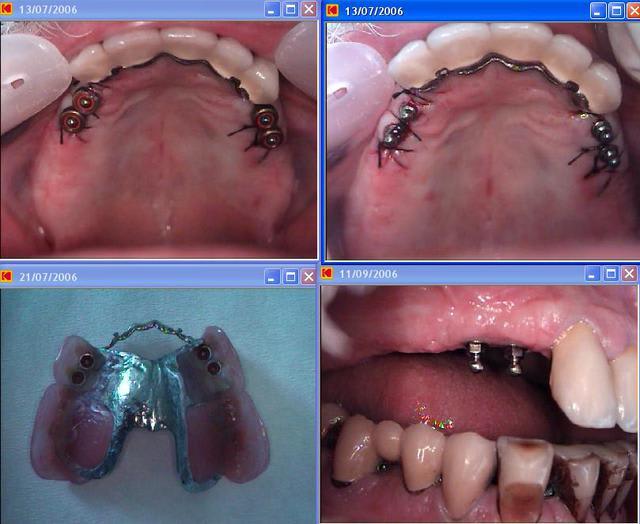

fait en 2006, toujours en place ( juste perdu un implant, tres rapidement, a cause d'une erreur :je n'avais pas meuler l'intrados de la resine au dessus de la boule, pour éviter la pression direct du stellite sur l'implant ).

ce sont des mini implant OBI euroteknika, en mise en charge immédiate.

Avec 2 implants 3.5 ostéointégré avant mise en charge, je pense que cela passe. Le plus important, c'est un stellite a selle disjointe : indispensable pour ce genre de travail.